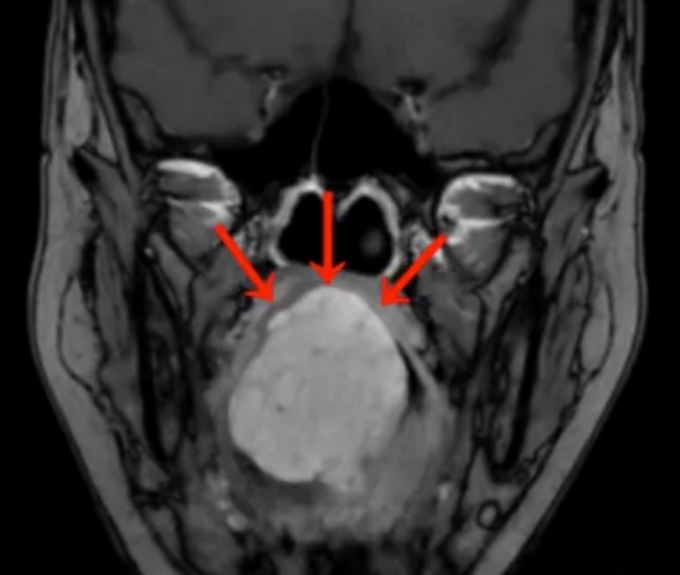

8月22日据媒体报道,刘女士到社区做核酸检测时,意外发现舌根下竟藏有一个巨大肿块。刘女士便于近日来到广州中山大学肿瘤防治中心求医,经诊断为舌根癌。

舌根癌是长在舌根部的恶性肿瘤,是上皮来源的恶性肿瘤,所以称为癌。可以分为几大类,常见的是鳞状上皮癌,还可以有腺癌、淋巴上皮癌等。因为长在舌根部也就是长在舌后1/3,在口腔当中不可以直接看到,所以很隐蔽,早期不容易被发现。而舌根癌早期又没有什么症状,一旦发现往往是中期或者晚期。因为早期没有症状,所以长的比较快,慢慢会出现疼痛,只有出现疼痛以后病人才能到医院就诊。到医院就诊可以拍摄CT,可以看到舌根部长了一个肿物,一般都是菜花样,如果比较大可能会影响吞咽或者咽部有异物感。如果得了舌根癌需要尽早进行手术治疗,根据病理情况配合其它治疗。